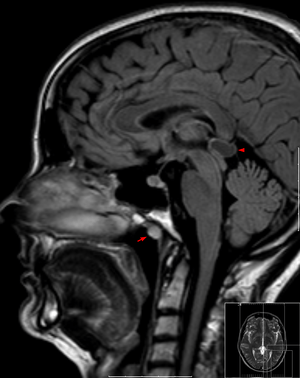

| Tornwaldt cyst imaged on sagittal MRI (FLAIR). The cyst appears hyperintense in the midline of the nasopharynx (arrow). In this case there is also a cyst of the pinealis gland (arrowhead) showing a signal intensity slightly higher than the CSF. | |

A Tornwaldt cyst is a benign cyst located in the upper posterior nasopharynx. It can be seen on computed tomography (CT) or magnetic resonance imaging (MRI) of the head as a well-circumscribed round mass lying in the midline. In most cases, treatment is not necessary. It was first described by Gustav Ludwig Tornwaldt.